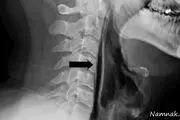

پارگی گلو مرد بیچاره بخاطر عطسه اشتباهی!+ عکس

اشتباه مرد 43 سال هنگام عطسه برایش گران تمام شد ، لحظاتی بعد دردهای شدید و حالت غیرقابل تحمل در بلع او را راهی بیمارستان کرد.